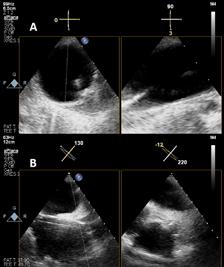

Ecocardiografia poate determina evaluarea fracției de ejecție a ventricului stâng (FEVS) ce permite distribuirea pacienților cu IC în una din clasele din cadrul clasificării funcționale NYHA. Ecocardiografia oferă și informaţii despre parametri precum: dimensiunile cavitaţilor cardiace - hipertrofie de ventricul stâng (HVS) excentrică sau concentrică, anomalii ale mișcării peretelui regional (care pot sugera patologie coronariană subiacentă, sindrom Takotsubo sau miocardită), funcţia ventricului drept (VD), hipertensiune pulmonară, funcţia valvulară și markerii funcţiei diastolice.6

HFrEF sau HFpEF, subliniind astfel terapia individualizată în funcție de fracția de ejecție a ventricului stâng. Efectuarea ecografiei cardiace cu încadrarea corectă a paciențior în categoriile propuse de definiția universală a IC înseamnă extinderea populației care poate beneficia de tratament optim în funcție de fenotipul existent.4,15